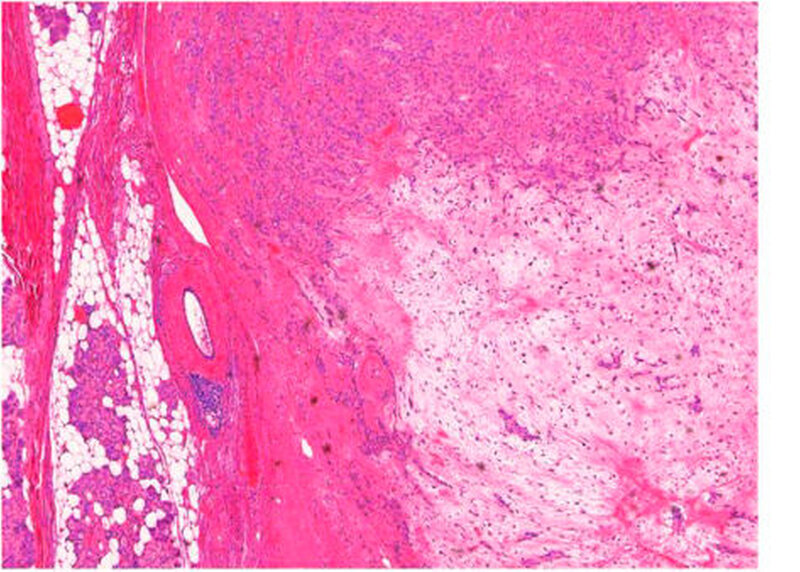

Die Untersuchung des eingesandten Weichgewebsresektats der Parotis rechts (Abbildung 7) ergab ein in sano entferntes pleomorphes Adenom neben regelhaft strukturiertem Speicheldrüsenparenchym mit mäßiger Lipatrophie (Abbildung 8) und insgesamt drei tumorfreien Lymphknoten. Es zeigte sich kein Anhalt für Dysplasie oder für Malignität.

Histologisch ist das pleomorphe Adenom durch eine sowohl strukturelle als auch zelluläre Pleomorphie mit epithelialen, myoephithelialen, mukoiden, myxoiden, hyalinen und chondroiden Anteilen gekennzeichnet [Ethunandan et al., 2006], weshalb der Tumor ehemals auch als „Misch-Tumor“ beschrieben wurde. Häufig wird der Tumor durch eine komplette oder inkomplette kapselartige Struktur umschieden. Dabei handelt es sich um eine Pseudokapsel mit feinen Ausläufern, die sich in das umgebende Gewebe fortsetzen. [Henrikkson et al., 1998; Phillips et al., 1995]